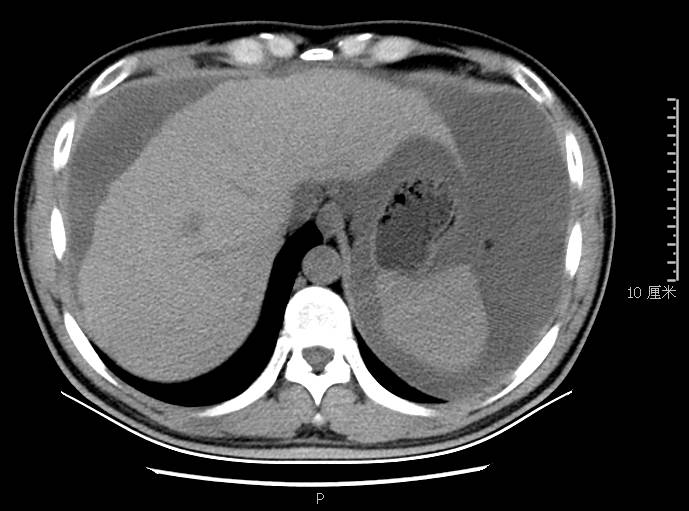

全腹CT:(1)结合病史考虑腹膜炎(见图2A),大量腹水;(2)右骼窝区管状样结构,考虑阑尾扩张(见图2B);(3)肝脏多发小囊肿(见图2C);(4)肝内胆管轻度扩张,建议隔期复查。

图2a大网膜成饼状(CT腹腔横断图象上出现肠曲被前面及两侧的肿瘤组织限制在中央

本例确诊后对B超及CT再次回顾发现:腹腔、盆腔可见不均质中强回声包块,部分呈囊实状,腹膜增厚,大网膜成饼状(如图2A)和肝周可见不均质中强回声弧形压迹、脾周可见不均质中强回声包饶,肝脏成扇贝样改变(如图2C),但在诊断报告中未提及。有学者发现mantle和scalloping(如图2A,2C)在PMP中具有代表性,且mantle较scalloping更为常见,若mantel征同时伴有大小不一的囊性改变,则更具诊断价值。

图2c肝脏成扇贝样改变(肝脏因为受肿瘤实质性或囊性组织压迫而其实质却未受侵犯,于是在一处或多处呈下凹状或扇形皱褶状(scalloping)